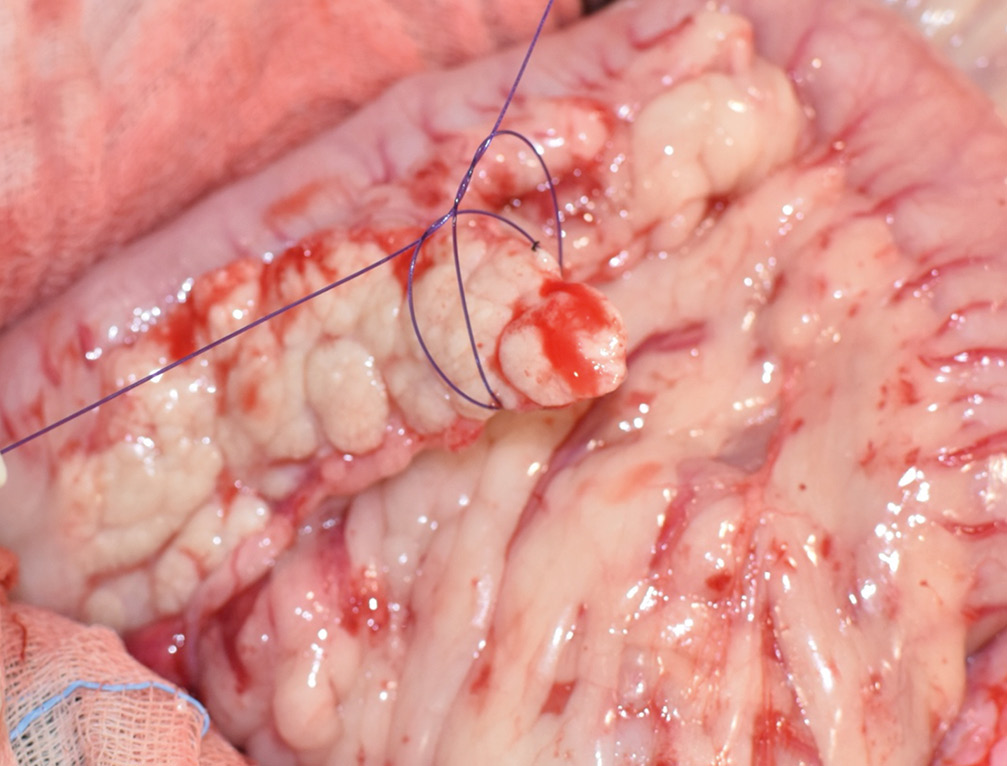

El tratamiento quirúrgico es el de elección para perros con enfermedad en estadio I (enfermedad localizada) o II (presencia de metástasis locorregional) e implica una pancreatectomía parcial para extirpar el tumor primario y cualquier metástasis visible (imágenes 4A-4K y 5A-5H). La mediana de supervivencia es más larga en los perros tratados quirúrgicamente en comparación con los perros tratados médicamente, como se describe en dos estudios donde la mediana del tiempo de supervivencia de los perros sometidos a pancreatectomía parcial fue de 381 días y 785 días, respectivamente, en comparación con 74 días y 196 días, respectivamente, en aquellos tratados solo con tratamiento médico.30 En otro estudio reciente, el tiempo medio de supervivencia registrado para 49 perros con insulinoma fue de 561 días y de hasta 746 días para perros que tuvieron resolución de hipoglucemia, con un tiempo medio euglucémico global (tiempos desde la cirugía hasta la primera detección de hipoglucemia en cualquier momento después de la cirugía) de 424 días para todos los perros.39

Imágenes 4A – 4K. Secuencia de imágenes quirúrgicas en un perro (con las imágenes del TC), durante una pancreatectomía total del lóbulo izquierdo y cuerpo del páncreas (usando la técnica de “guillotina” sutura/fractura con el nudo de Miller modificado) y resección de NNLL centinelas, por insulinoma en el cuerpo del páncreas.

Imágenes 5A – 5H. Secuencia de imágenes quirúrgicas en un perro (con las imágenes del TC), durante una pancreatectomía total del lóbulo derecho y parte del cuerpo del páncreas (usando la técnica de “guillotina” sutura/fractura con el nudo de Miller modificado) y resección de NNLL centinelas, por insulinoma en el lóbulo derecho del páncreas.

El tratamiento recomendado es la escisión quirúrgica. Aunque no suele ser curativa, los esfuerzos para extirpar todo el tumor primario macroscópico y la enfermedad metastásica reducirían la carga tumoral general. Esto, a su vez, puede ayudar a controlar la hipoglucemia, prolongar el tiempo libre de enfermedad y mejorar la supervivencia. El procedimiento quirúrgico consiste en una pancreatectomía parcial, eliminando todo el tejido neoplásico que pueda ser identificado (un 5 % corresponde a carcinoma de islotes difuso microscópico, detectable por palpación) junto con los NNLL centinelas +/- resección de nódulos hepáticos si estuvieran presentes.20 La hipoglucemia persistente tras la cirugía se ha considerado como factor negativo (signo de metástasis o resección incompleta).4

- Sección con sutura – fractura (guillotina): especialmente indicada en tumores localizados en la extremidad de los lóbulos pancreáticos o en los bordes del parénquima, en enfermedades difusas y en traumatismos (imágenes 9A y 9B). Para exponer el tejido, se libera el mesoduodeno u omento y la vascularización circundante. Se coloca una lazada de sutura monofilamento absorbible alrededor del tejido que se va a biopsiar que, al anudar, secciona el parénquima ocluyendo los conductos y vasos. Finalmente, se resecciona la muestra mediante bisturí a unos milímetros de la ligadura y se procede al lavado y cierre del mesoduodeno u omento.1 Realizar lavados locales ayuda a disminuir las proteasas intraperitoneales. El sangrado difuso se puede controlar con parches de colágeno.